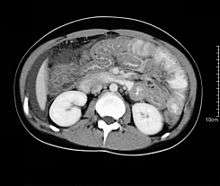

CT scan may show nodular and irregular thickening of the folds in the distal stomach and proximal small bowel, but these findings can also be present in other conditions like Crohn's disease and lymphoma.